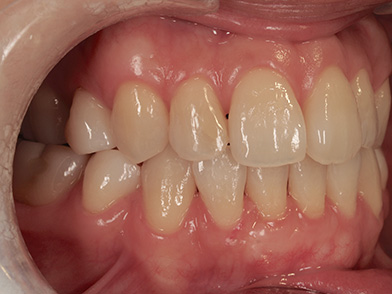

正面から見た口中の写真

水色矢印の部分が対象部位です。歯ぐきがやせてしまい、歯根(歯の根)が見えてしまっています。このままにしておくと、見た目の問題はもちろん歯がしみたり、虫歯になりやすいなど問題が悪化する恐れがあります。また歯ぐきが薄いため、歯ブラシなどの摩擦刺激でさらに歯ぐきがやせてしまう恐れがあります。緑色矢印が手術により再生された部分となります。ご自身の歯ぐきを移植することで、拒絶反応も少なく良好な結果を得ることができています。右側にまだ歯ぐきがやせてしまっている部分が残っていますが、少しずつ自分のペースで治療をされており、現在継続中の患者様です。

治療前

治療後(手術後2年経過)